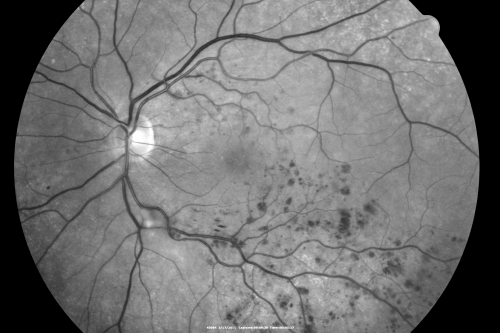

Macular Branch Retinal Vein Occlusions (2) Left Eye - No Macular Edema (yet)

77-year-old woman with two macular branch retinal vein occlusions in the left eye OD 20/25